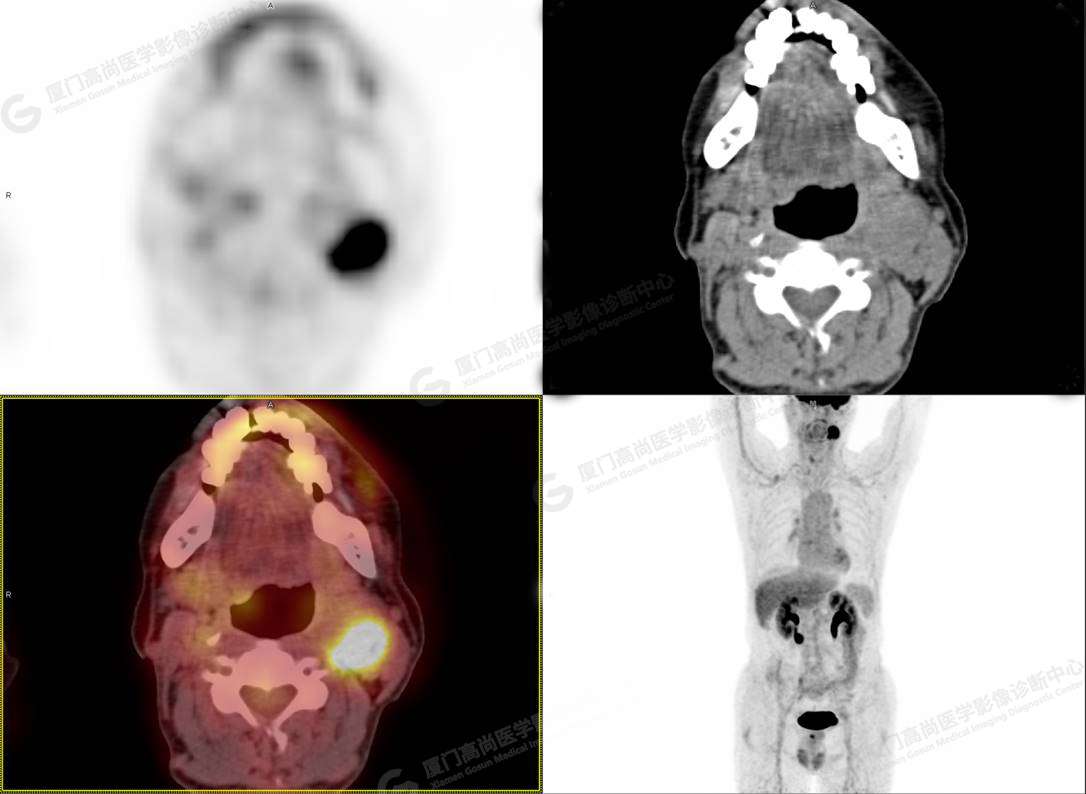

圖3

PET/CT所見:左側(cè)頸部(II區(qū))見腫大淋巴結(jié),大小約2.5cm×2.3cm,其內(nèi)密度不均,邊界尚清,放射性攝取異常增高,早期SUVmax 11.5,延時SUVmax 14.5。

影像診斷: 左側(cè)頸部(II區(qū))腫大淋巴結(jié),代謝異常增高,考慮腫瘤性病變可能性大(淋巴瘤?轉(zhuǎn)移瘤?),建議病理學(xué)檢查明確。